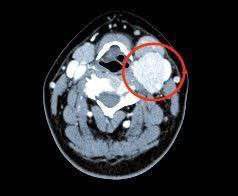

Врачи нижегородского онкоцентра спасли пациентку с редкой опухолью шеи Сосудистое новообразование называется каротидная хемодектома Часто появляется ещё в молодости и никак не заметна долгое время Из за такой опухоли человеку становится трудно дышать и глотать потом меняется голос начинаются боли и кровотечения Самое сложное в операции то что рядом находятся сосуды питающие головной мозг Малейшая неточность и человек может остаться инвалидом У хирургов всё получилось на контрольном приёме рецидивов у больной не было mynnovgorod